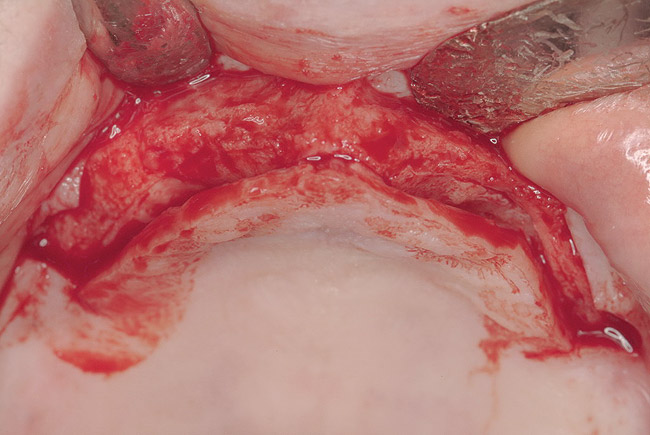

Figure 10  Full-thickness flap of edentulous maxillary arch.

Figure 10

These patients were tested for two different treatment options; either a bar-supported overdenture requiring four implants in the first premolar area or anterior to the bicuspids, or a "simple fixed prosthesis" anchored by six implants placed bilaterally from first-molar-to-first-molar regions. When a flapless, guided surgery was contemplated, the investigators determined that based on the available maxillary bone, 70% of patients (28 implants) could undergo this treatment modality. Of the 40 patients, 15% could not have any implants placed due to inadequate bone height and width. For "simple fixed prostheses," only 30% (72 implants) of patients presented with adequate bone dimensions permitting a flapless guided placement of six maxillary implants placed symmetrically around their arch in a flapless manner. For the fixed treatment, 18% of patients could not have any implants placed due in insufficient bone dimensions. The authors concluded that advertisement of computer-guided, flapless solutions are "euphoric," and tend to overlook patients' individual oral and anatomic conditions. They felt that guided surgery does provide better control of implant placement leading to higher predictability of treatment outcomes. In a study where the accuracy of virtually placed implants and actual positions in a cadaver model were compared, Petterson et al7 found significant differences related to deviations in hex, apex, and depth of the two placements. Without the preparedness to temper treatment expectations or plan on delivery of the pre-fabricated "final" prosthesis immediately after surgery, these types of studies should lead clinicians to proceed with caution in these procedures. The efficacy of an open approach, one requiring a mucoperiosteal flap, may be improved upon with a guided approach in cases where severe ridge-resorption is treated, and may be more predictably handled using this technology. A bone-supported template, affixed to the alveolar ridge with fixation screws, can be fabricated with numerous software package and stereolithography (Figure 8 and Figure 9). A full-thickness flap is elevated, exposing the resorbed alveolar ridge (Figure 10). Using osseous fixation screws, the template is stabilized to the ridge, preventing any movement during osteotomy preparation (Figure 11). Using a sleeve-in-sleeve, manufacturer-specific surgical armamentarium, implants can be placed in the optimal positions, where the maximum amount of initial bone to implant contact is achieved. The anticipated bone augmentation procedures can then be performed, which is not possible with a closed procedure (Figure 12). The flaps are subsequently closed, allowing for the patient to wear any transitional, soft-relined denture. The surgical guide can also serve an important function at the time of implant uncovering. The location of the implants beneath the healed mucosa can be determined by seating the guide and sounding with a 30-gauge anesthetic needle. Using a tissue punch, the implants can be uncovered without flap elevation; the cover screws can be removed and the appropriately sized healing abutments can be placed (Figure 13). From this point forward, traditional prosthetic steps are followed to fabricate an implant-supported/retained overdenture.